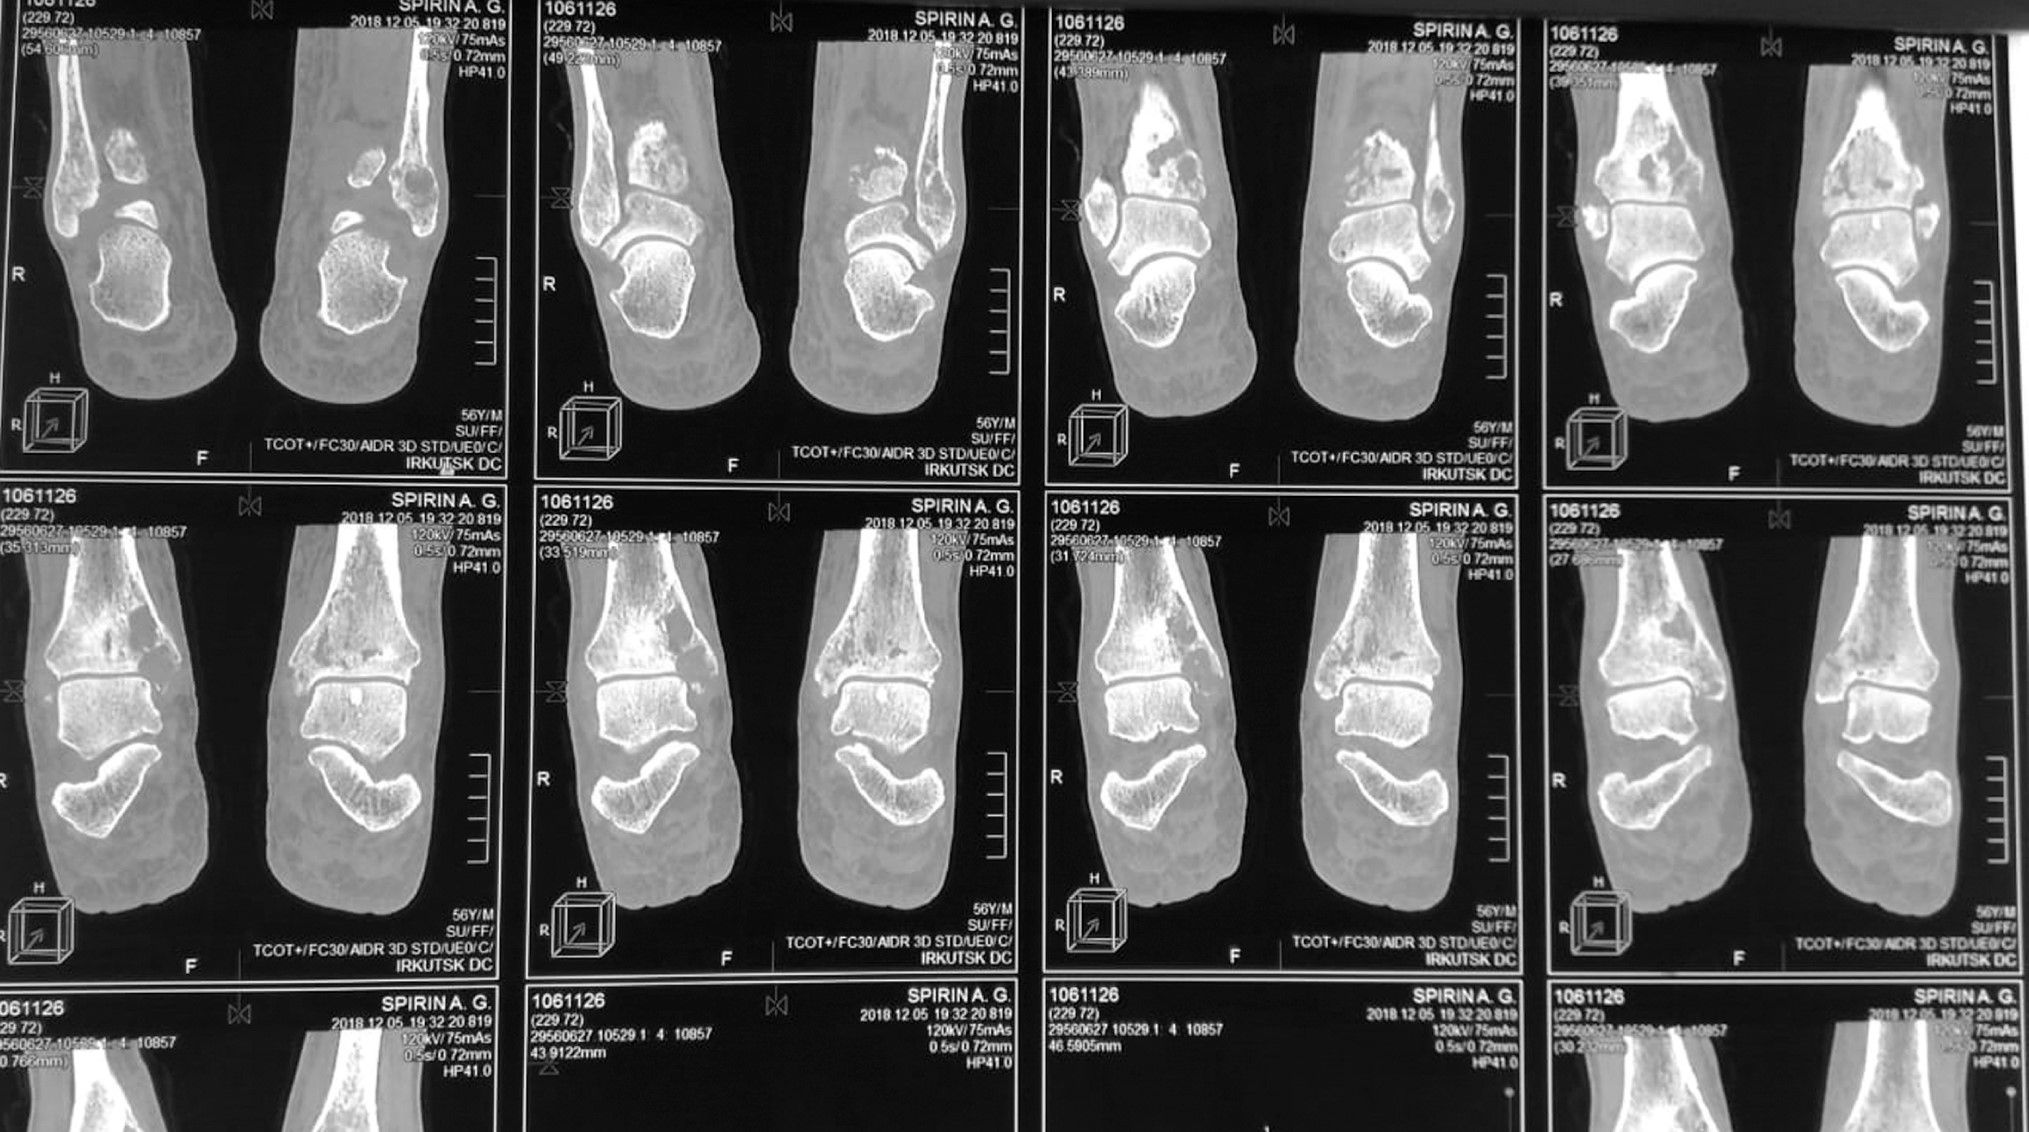

Instrumental examination. Multispiral computed tomography on 12.05.2019: cystic transformation, volume-occupying mass lesions and osteolysis in the distal areas of both tibial bones (Fig. 1). Chest cavity X-ray dated 16.05.2019: diffuse pneumosclerosis. Ultrasound examination of the abdominal cavity organs dated 20.05.2019: no signs of structural abnormalities.

Fig. 1. Multispiral computed tomography: osteolytic destructive changes in the distal areas of the tibial bones.